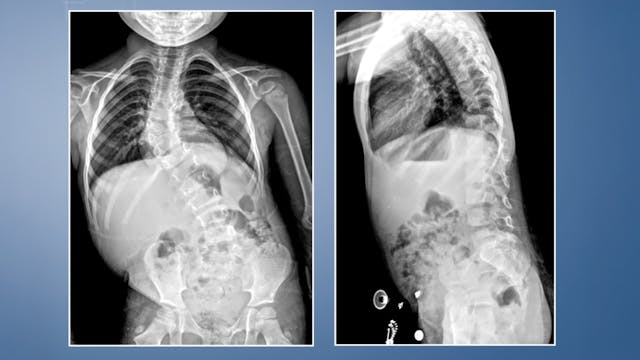

Resection of Thoracic Hemivertebra in Congenital Scoliosis